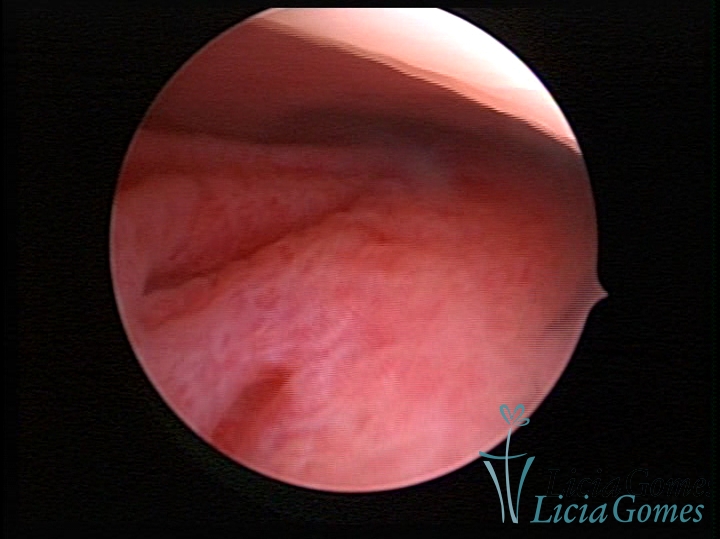

PÓLIPOS ENDOCERVICAIS

São tumores benignos, resultantes da proliferação focal reativa aos processos inflamatórios ou à situações de hiperestrogenismo, e podem ter sésseis (com a base de implantação larga) ou pediculados do epitélio.